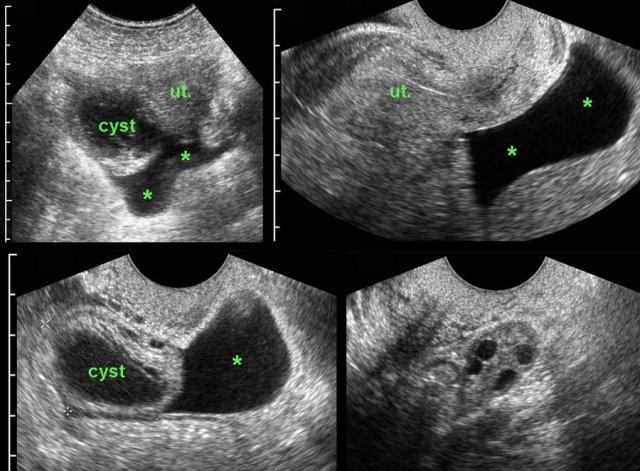

Ca lâm sàng 3

Các hình ảnh này của một phụ nữ 17 tuổi với cơn đau hố chậu phải cấp tính, dữ dội. CRP bằng 1.

Siêu âm phát hiện một nang buồng trứng phải thành dày, bờ không rõ và dịch tự do (*) trong túi cùng Douglas.

TVUS xác nhận hình ảnh dịch và một nang xẹp một phần, dễ ép xẹp ở buồng trứng phải.

Buồng trứng trái bình thường (hình dưới bên phải).

Cơn đau giảm dần và các xét nghiệm duy trì trong giới hạn bình thường.

Trong vòng một tuần, hình ảnh siêu âm hoàn toàn trở về bình thường.

Chẩn đoán có khả năng nhất: nang chức năng vỡ.